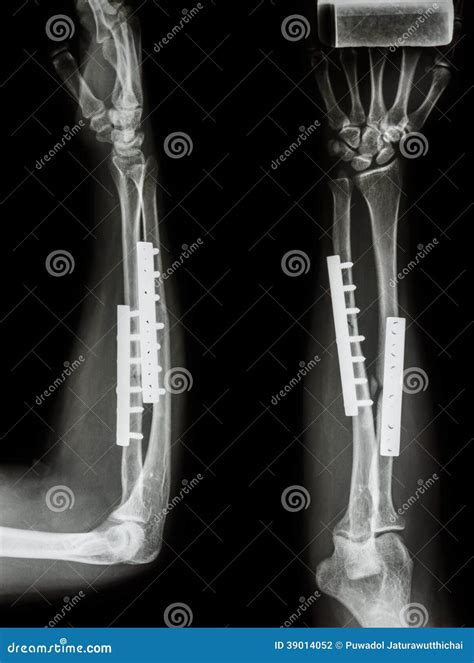

• Open Reduction and Internal Fixation (ORIF): The bone is realigned and held in place with plates, screws, or rods.

• External Fixation: Metal pins or screws are inserted into the bone and connected to an external frame to stabilize the fracture.